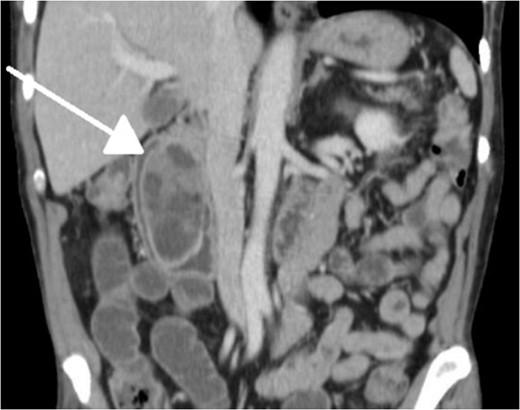

With regard to diagnostic workup, the literature has described cases with similar results to ours. Small bowel contrast studies frequently show smooth-walled polypoid filling defects within the duodenal bulb, and CT imaging is useful for delineation of adjacent structures including the common duct and pancreas [1]. Moreover, similar to the pathological results found in our patient, upper endoscopy biopsies are often equivocal as they are submucosal-based lesions [1]. The most useful diagnostic study, however, is endoscopic ultrasound, which may help distinguish the consistency and bowel layer of origin [2, 6], which unfortunately was not available at our institution.